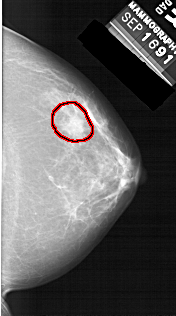

A_1456_1.RIGHT_CC

RIGHT_CC LINES 5356 PIXELS_PER_LINE 2986 BITS_PER_PIXEL 12 RESOLUTION 43.5 OVERLAY

FILE: A_1456_1.RIGHT_CC.OVERLAY

TOTAL_ABNORMALITIES 1

ABNORMALITY 1

LESION_TYPE MASS SHAPE IRREGULAR MARGINS ILL_DEFINED

ASSESSMENT 4

SUBTLETY 2

PATHOLOGY BENIGN

TOTAL_OUTLINES 1

BOUNDARY